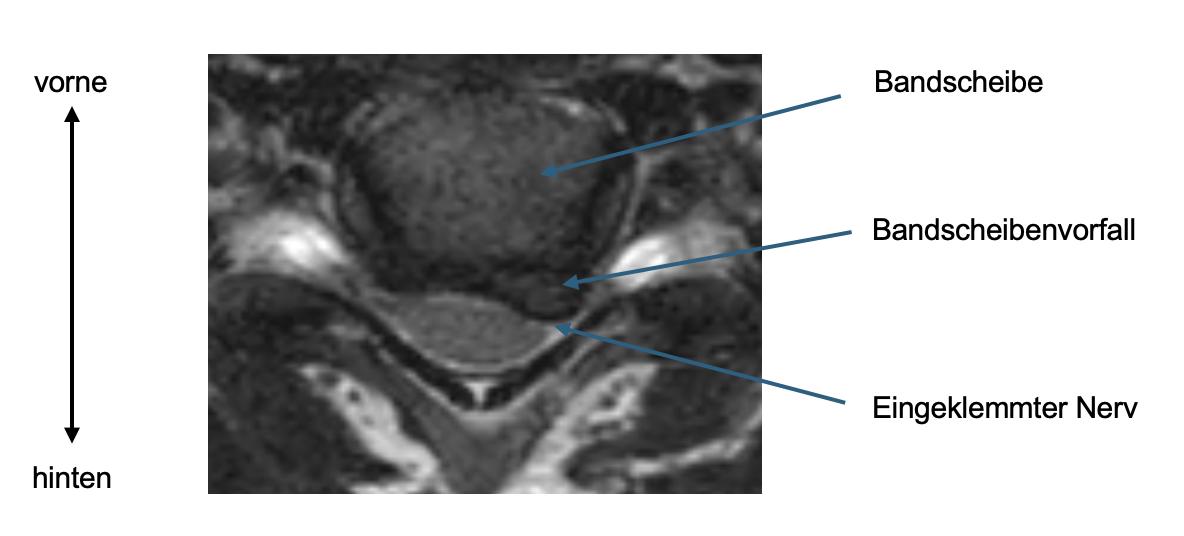

Die Bandscheiben (Diskus) sind ovale "Polster" welche zwischen den Wirbelkörpern liegen. Sie bestehen aus einem äusseren derben Ring aus Faserknorpel (Anulus fibrosus) und einem relativ weichen Kern (Nukleus). Prinzipiell erfüllen sie 3 wichtige Funktionen: Sie federn die Last des Körpergewichts ab, sie ermöglichen eine Beweglichkeit zwischen den Wirbeln als eine Art Kugellager und sie verbinden gleichzeitig die Wirbelkörper miteinander und sorgen so für die Stabilität des Segments (2 angrenzende Wirbel).

Im Falle eines Risses des äusseren Rings (Anulus) kann der Kern oder Teile von ihm austreten und auf einen oder mehrere Nerven drücken.